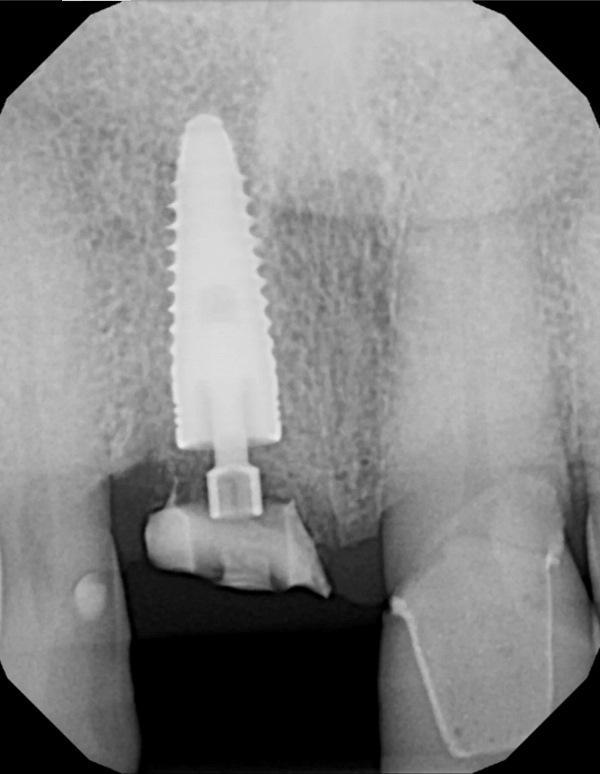

Выполнена прицельная рентгенограмма для проверки посадки формирователя десны и документирования позиции имплантата относительно анатомических структур (Фото 6). Для содействия формированию сгустка между мягкими тканями и «липкой костью» на десну наложено давление. Наложены швы 4-0 из кетгута для удержания мягких тканей в контакте с индивидуальным формирователем десны. В полости рта установлен временный ретейнер Essix; пациенту предписано носить его круглосуточно, снимая только для проведения гигиены, до следующего приема через 2 недели (Фото 7).

Фото 6. Прицельная рентгенограмма после установки индивидуального формирователя десны и гребневой костной пластики; документирована позиция имплантата относительно окружающих структур и глубина его расположения от уровня гребня.